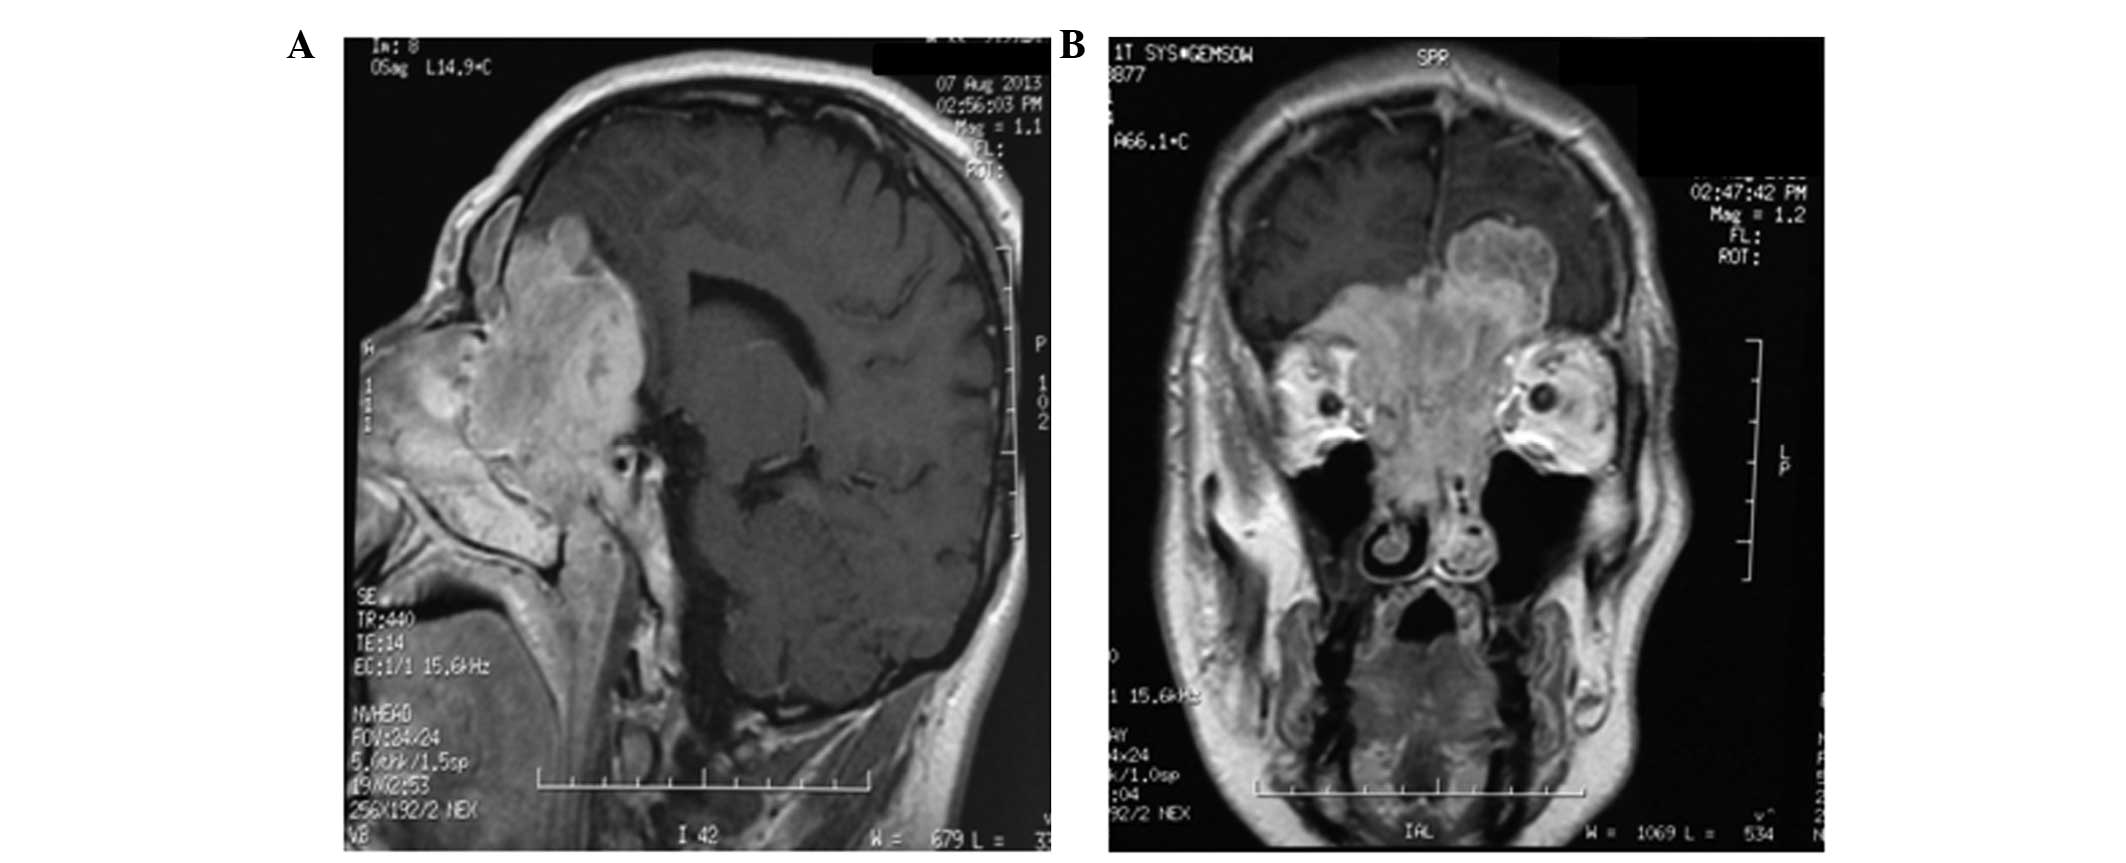

Ewing's sarcoma (ES) is an aggressive tumour that may present with skeletal and extraskeletal forms. The extraskeletal form is rarely encountered in the head and neck region and is extremely rare in the sinonasal tract. This is the case report of a ES of the ethmoid sinus with intracranial and orbital extension in a 33‑year‑old male patient who presented with anosmia, epistaxis, reduction of visual acuity in the left eye and headache. On otorhinolaryngological clinical examination and biopsy via flexible endoscope, the lesion was misdiagnosed as ethmoid sinus carcinoma. The subsequent magnetic resonance imaging (MRI) of the brain revealed a large mass (6x7 cm) eroding the ethmoid and sphenoid sinuses, extending beyond the orbits and occupying the anterior cranial fossa with a maximum extension of ~5 cm. The patient underwent surgical resection and the microscopic examination of the specimen established the diagnosis of ES (immunohistochemically positive for CD99, neuron‑specific enolase, CD56, synaptophysin, pancytokeratin, low‑molecular weight cytokeratins and vimentin. The periodic acid Schiff stain exhibited strong intracytoplasmic block positivity and fluorescence in situ hybridization revealed a t(22;11) translocation. first‑line chemotherapy was administered for 3 cycles; however, on restaging MRI, local disease progression was diagnosed. The patient received radiotherapy and second‑line chemotherapy for 6 cycles. At 15 months after the diagnosis, the patient remains recurrence-free and maintains a good functional status and quality of life.